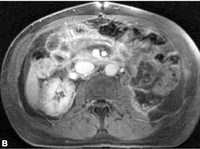

1例60岁男性患者左肾切除后发生急性肾功能衰竭,采用钆整合物进行增强MR显像示:A.术前两肾正常灌注;B.术后2天,患者发生急性缺血性肾衰竭。右肾示髓质灌注不良;皮质边缘灌注减低;C.随访3周显示,右肾灌注均匀,完全康复。